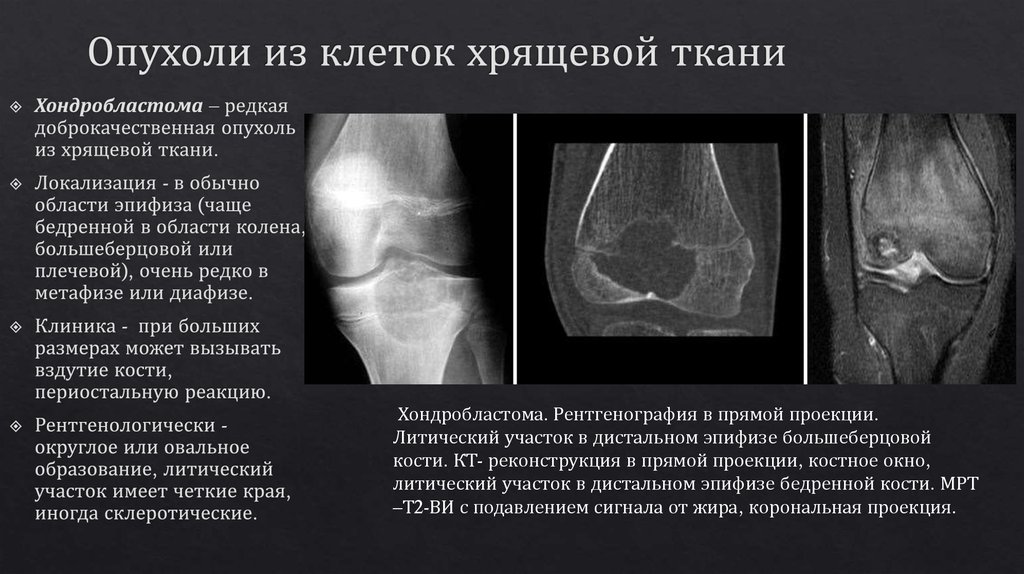

Рентгеновские снимки доброкачественных опухолей костей

Раздел: Моменты озарения